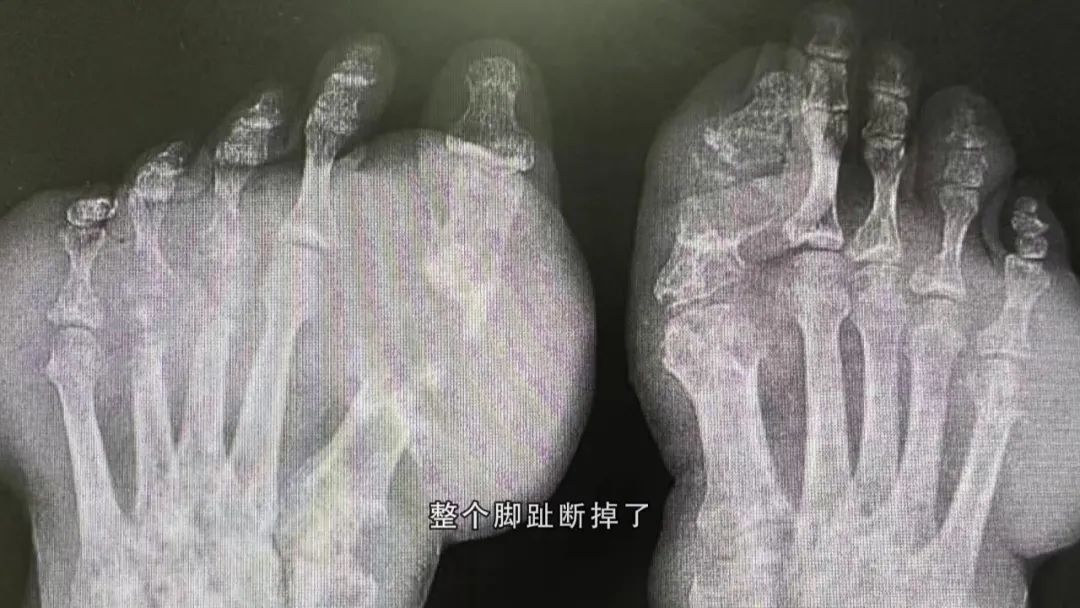

广医二院风湿免疫科主任医师于水莲表示,我们知道软骨是没有痛觉的,拿刀切它都不会痛,一旦软骨破坏之后,就会出现软骨下的骨侵蚀。有些患者的痛风石长在第一根大脚趾,就是第一指趾关节,拍了X光片甚至可以看到整个脚趾断掉了,这就是所说的痛风骨侵蚀。